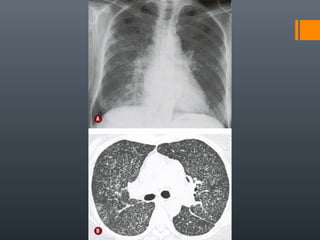

O documento discute vários conceitos radiológicos incluindo consolidação, atelectasia, nódulos, pseudocavidades e padrões intersticiais, fornecendo definições, sinais e diagnósticos diferenciais para cada tópico. Ele também discute a redução da atenuação pulmonar e fornece um link para mais informações.